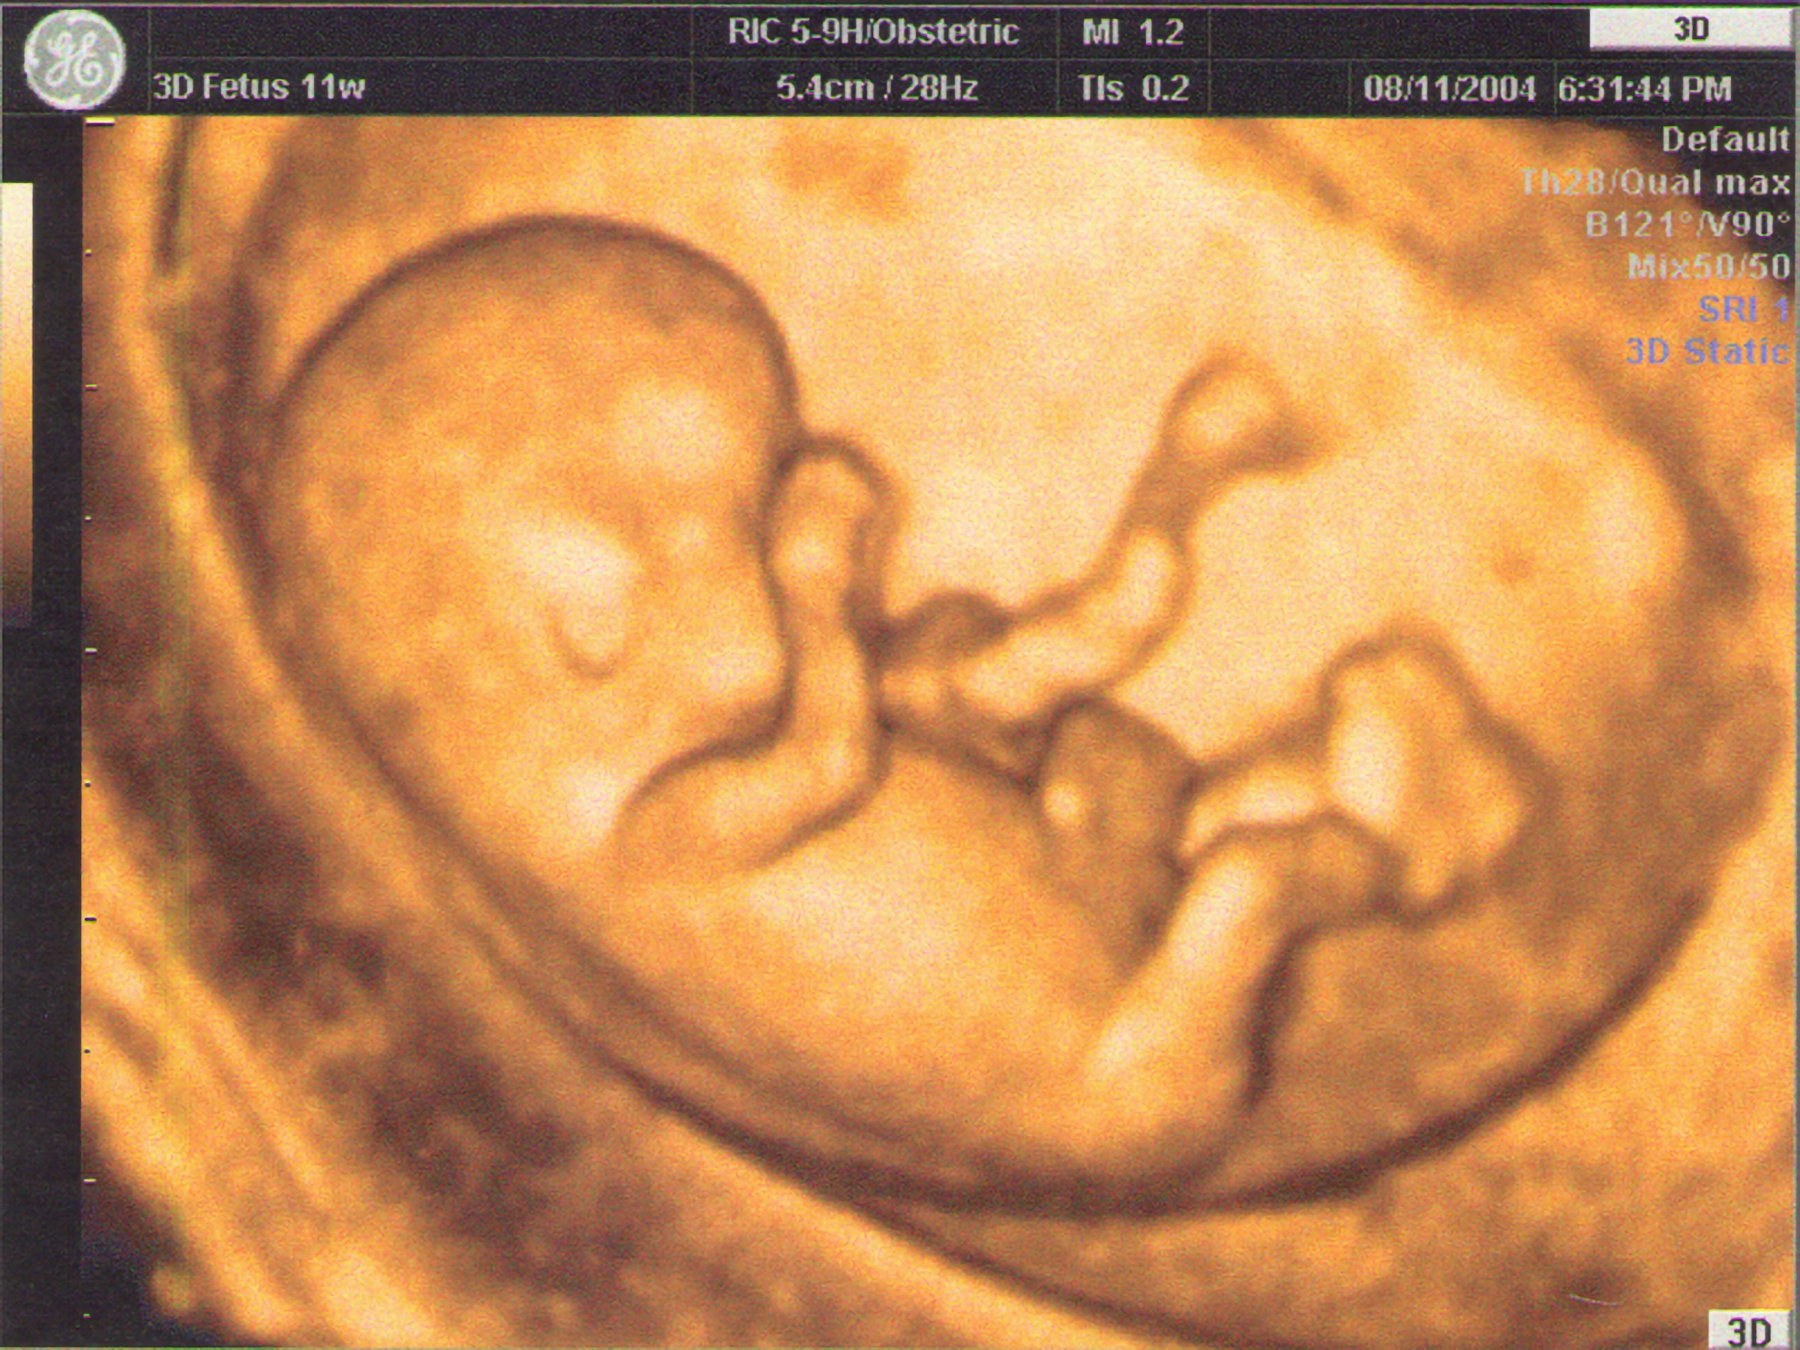

Gallery ECO